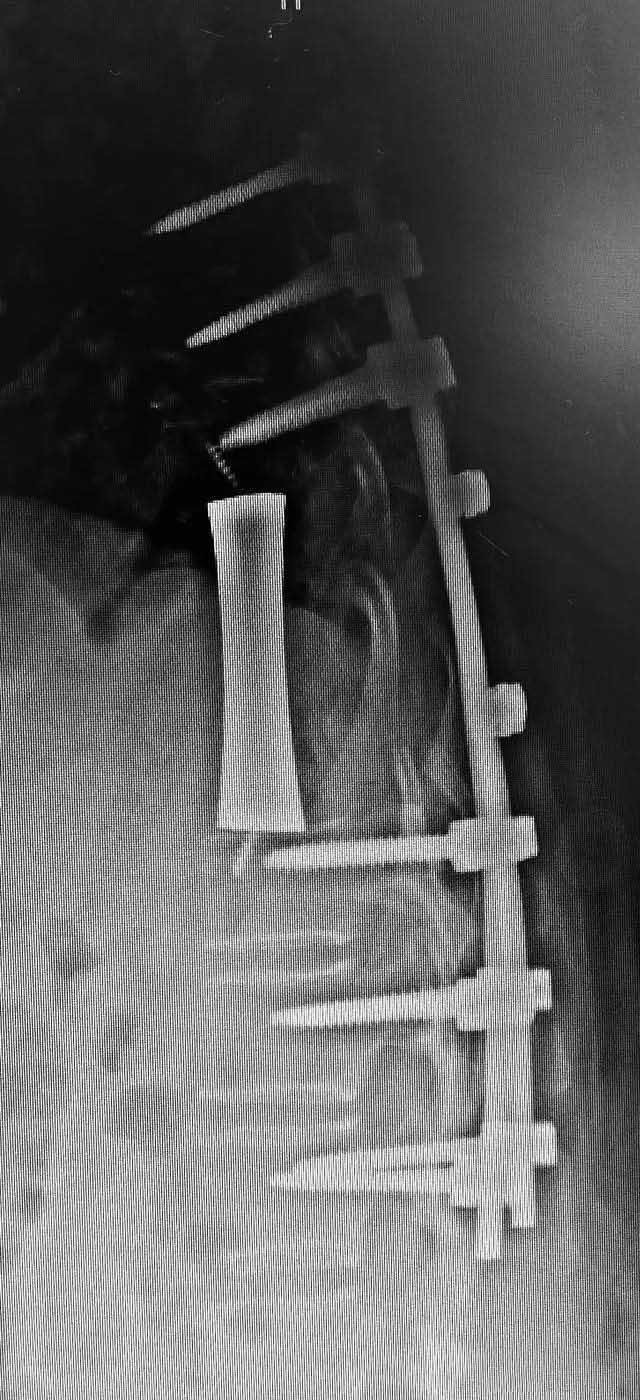

为了对李桦的脊椎恶性肿瘤切除后缺损进行精准重建,西京医院骨科李靖副教授团队联合相关科研院所和装备研发公司组成的科研联合攻关团队,根据CT数据设计个体化长节段椎体,并完成钽金属椎体的3D打印。手术当日,李靖主刀实施三节段脊柱肿瘤后路整块切除,同时采用3D打印的钽金属椎体进行支撑重建。由于个体化设计假体的良好匹配,重建过程非常顺利,手术全程耗时4小时。术后,李桦脊髓压迫完全解除,神经功能恢复正常,术后一周下地自由行走。

据了解,钽金属是目前医学界公认生物相容性最好的人体硬组织植入材料。但由于钽金属熔点高和钽粉价格高的特点,钽金属的3D打印增材制造在技术和经济层面都有困难。西京医院骨科李靖副教授团队联合相关科研院所和装备研发公司,以临床应用需求为牵引,开展数字化建模、生物力学设计研究,并在此基础上,通过采用全球唯一的大功率等离子旋转雾化制粉装备,制备出价格适中的高品质球形钽粉。与此同时,科研联合攻关团队进一步在自主研发的国产高精度电子束3D打印装备上,解决了高熔点钽金属精准熔化的难题,快速高效打印出个体化钽金属假体,为骨缺损增材制造中的异形性、骨长入和力学问题提供了解决方法。